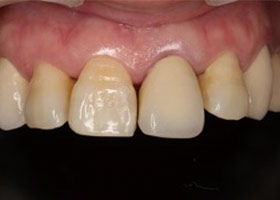

治療前門牙特寫、切端特寫照,發現假牙略微暴牙。

假牙完成後,門牙特寫、切端特寫照,暴牙已不復見。